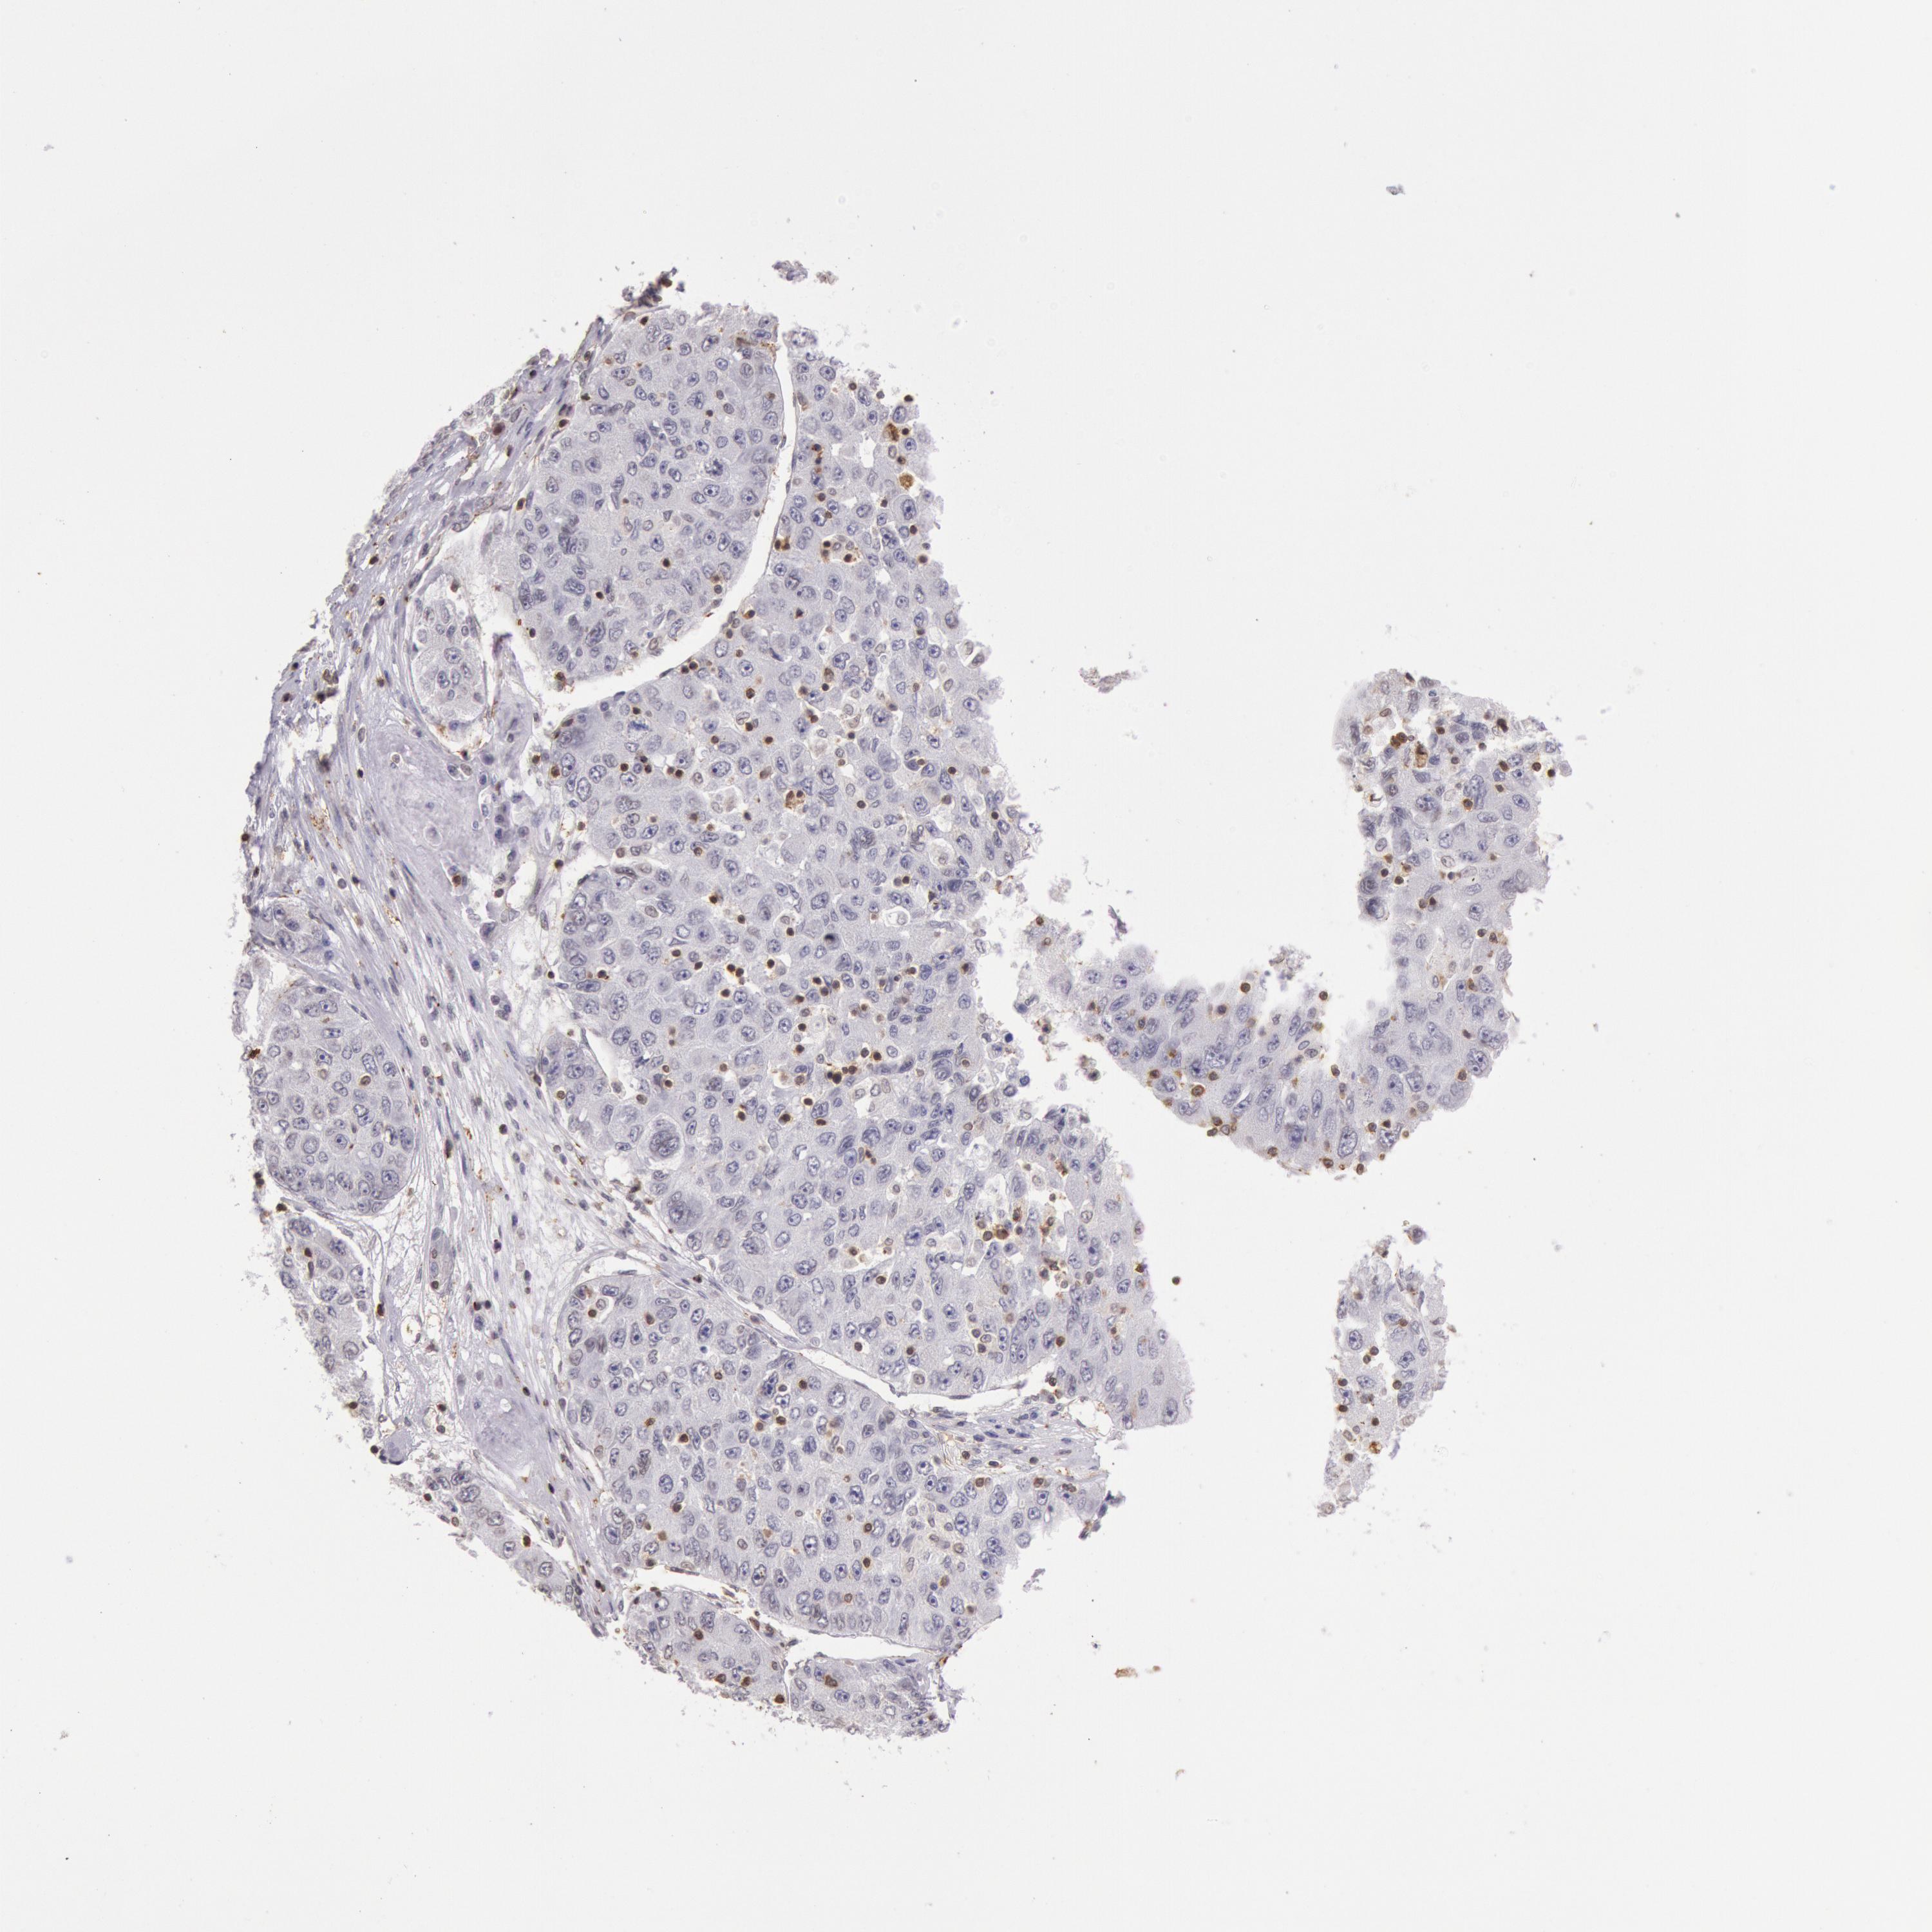

LIVER CANCER - Protein expressioni

A mouse-over function shows sample information and annotation data. Click on an image to view it in a full screen mode. Samples can be filtered based on level of antibody staining by selecting one or several of the following categories: high, medium, low and not detected. The assay and annotation is described here.

Note that samples used for immunohistochemistry by the Human Protein Atlas do not correspond to samples in the TCGA dataset.

Antibody stainingi

Antibody staining in the annotated cell types in the current human tissue is reported as not detected, low, medium, or high, based on conventional immunohistochemistry profiling in selected tissues. This score is based on the combination of the staining intensity and fraction of stained cells.

Each image is clickable and will lead to virtual microscopy that enables deeper exploration of all samples and also displays staining intensity scores, fraction scores and subcellular localization as well as patient and tissue information for each sample.

Antibody HPA001275

Antibody CAB017442

Staining

High

Medium

Low

Not detected

Intensity

Strong

Moderate

Weak

Negative

Quantity

>75%

75%-25%

<25%

None

Location

Nuclear

Cytoplasmic/membranous

Cytoplasmic/membranous,nuclear

Carcinoma, Hepatocellular, NOS

Cholangiocarcinoma